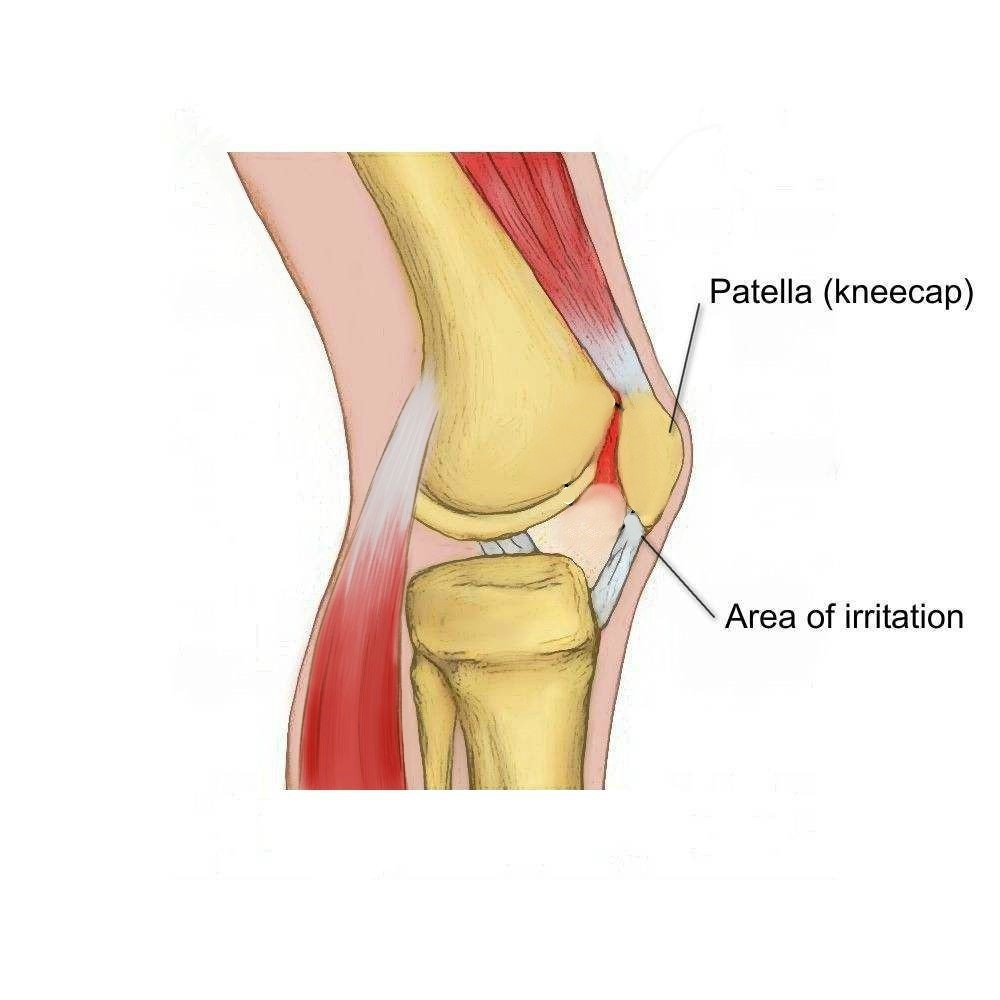

Возможные причины болей в ноге ниже колена и рекомендации